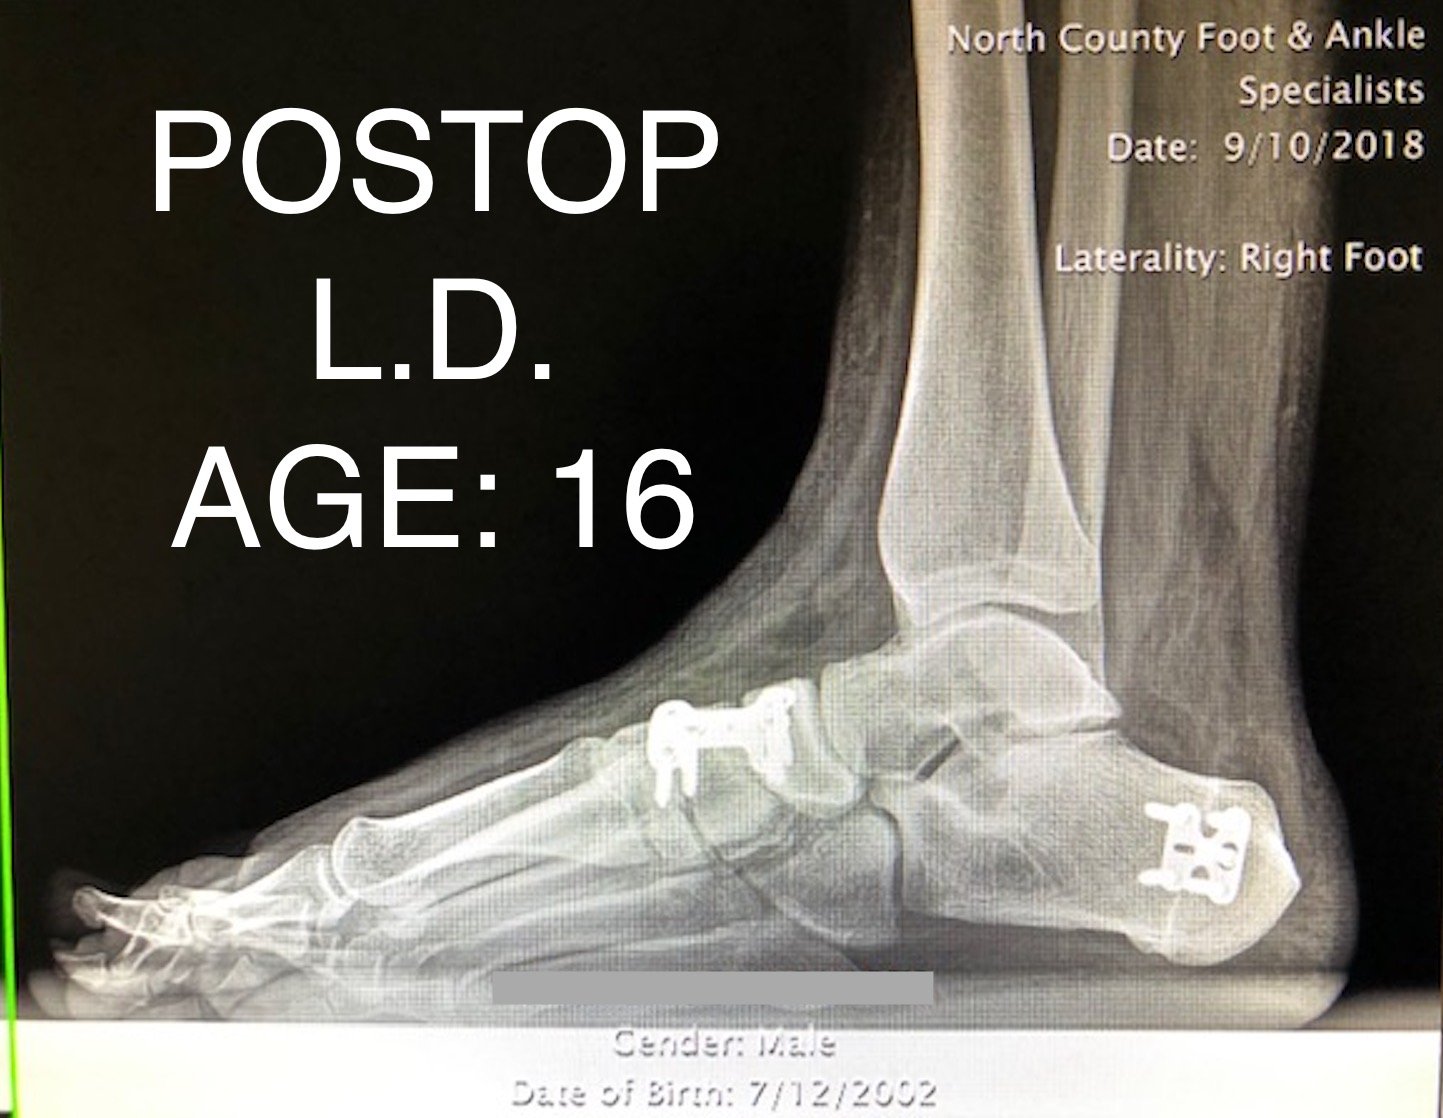

PEDIATRIC FLAT FOOT